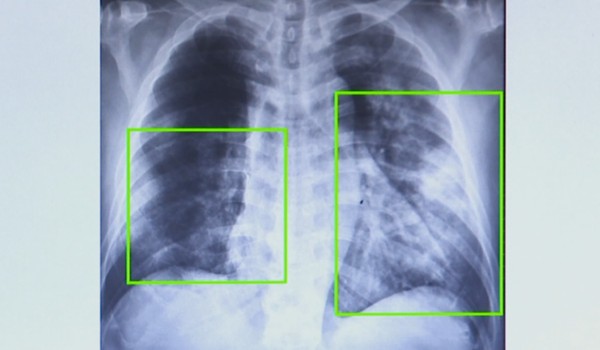

Atendimentos por pneumonia quase dobram em 7 meses na região de Campinas. — Foto: Reprodução EPTV

Casos de pneumonia aumentam 20% em SP; vacina contra a doença é oferecida de graça no SUS